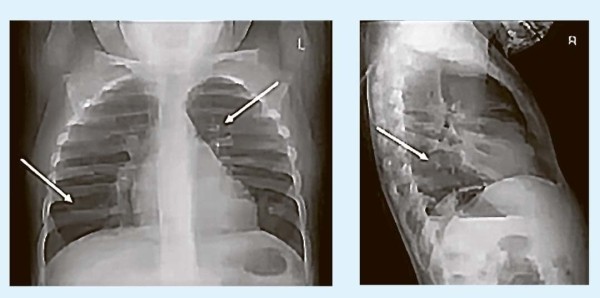

Рентгенография выполняется для исключения пневмонии.

— Специфических изменений на рентгенограмме при бронхиолите нет (см. рис. 1), — подчеркнул Павел Бережанский. — Отмечается вздутие легких (ребра расширены, практически горизонтальны), усиление бронхососудистого рисунка, участки понижения прозрачности легочной ткани, мелкие ателектазы, которые иногда ошибочно принимают за пневмонию, что ведет лишь к необоснованному назначению антибиотиков.